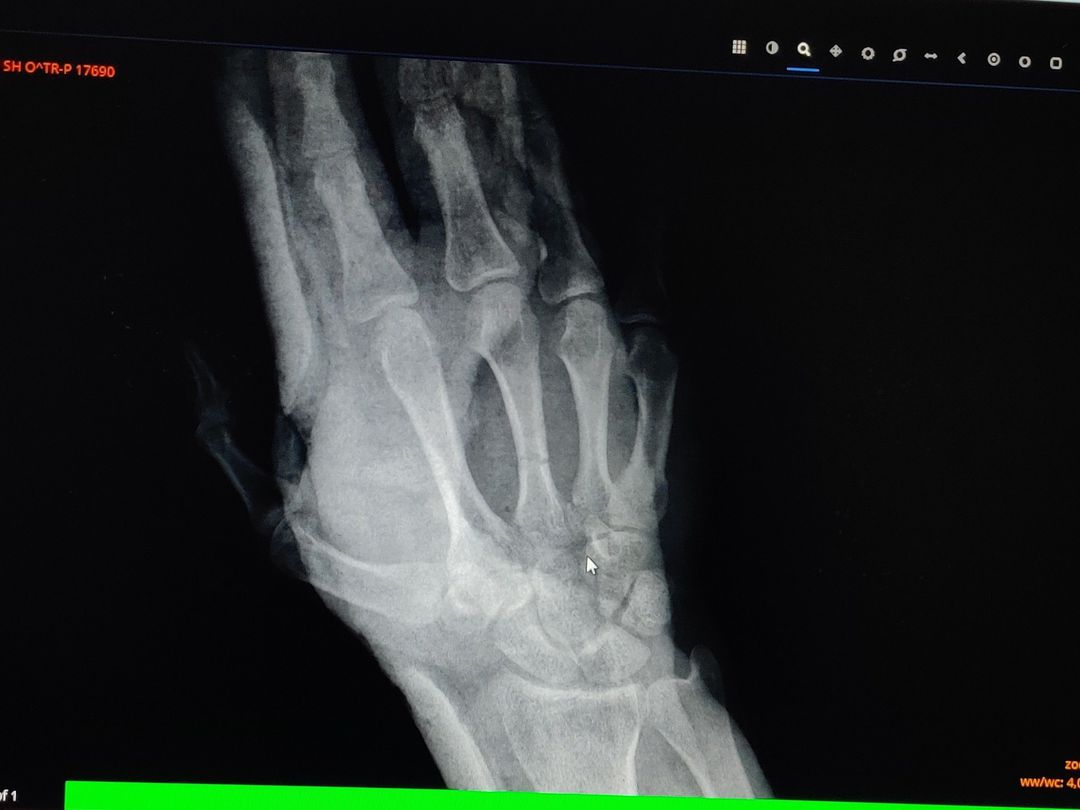

After reposition

Trauma

Xray

Traumatology